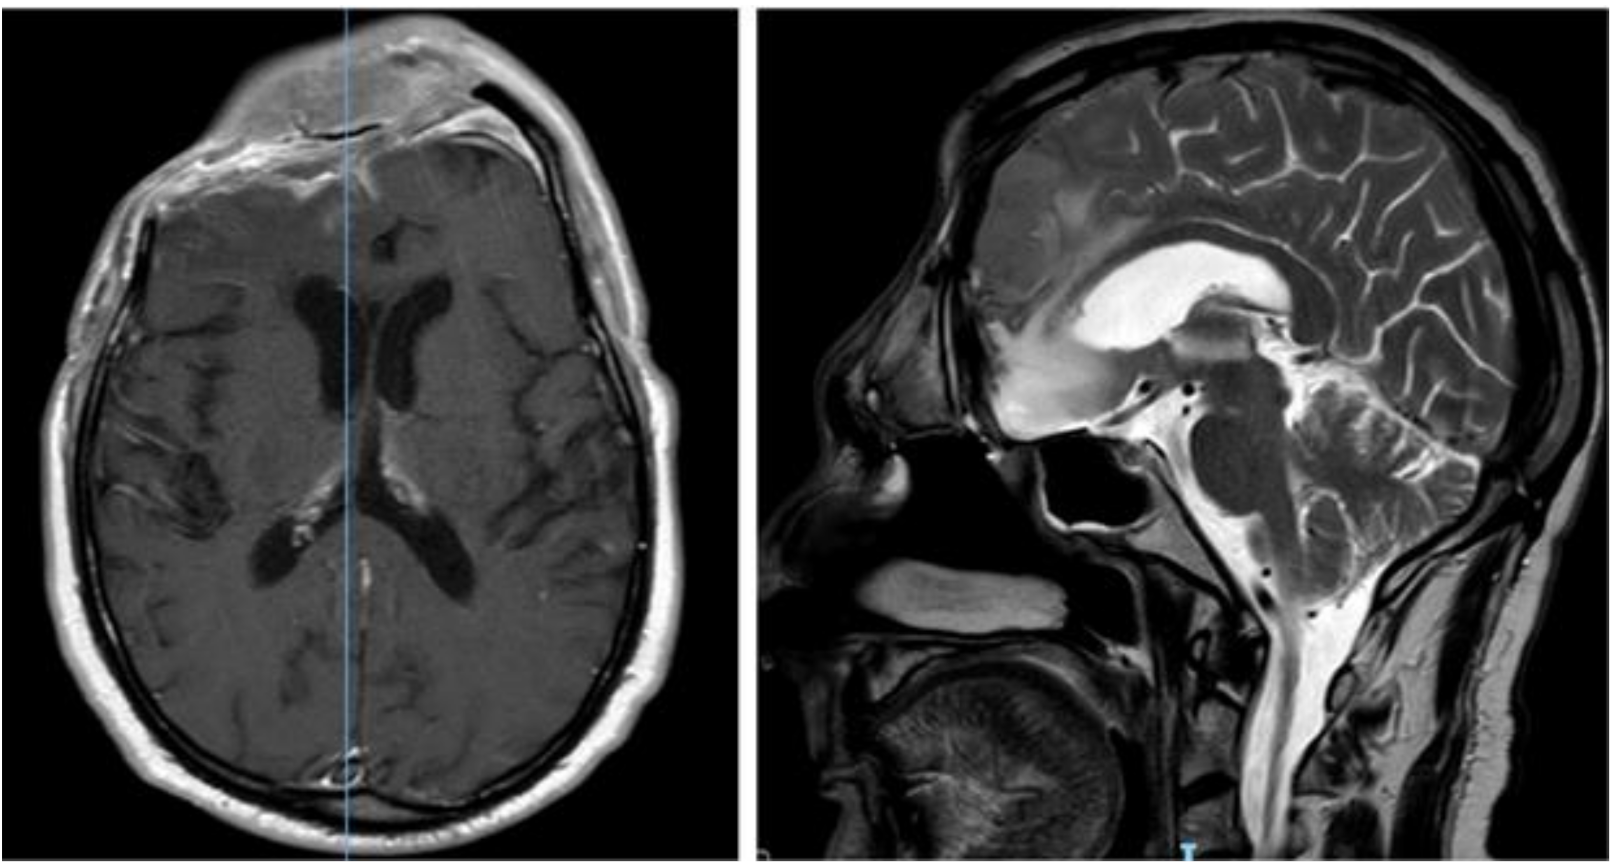

2. Case Report